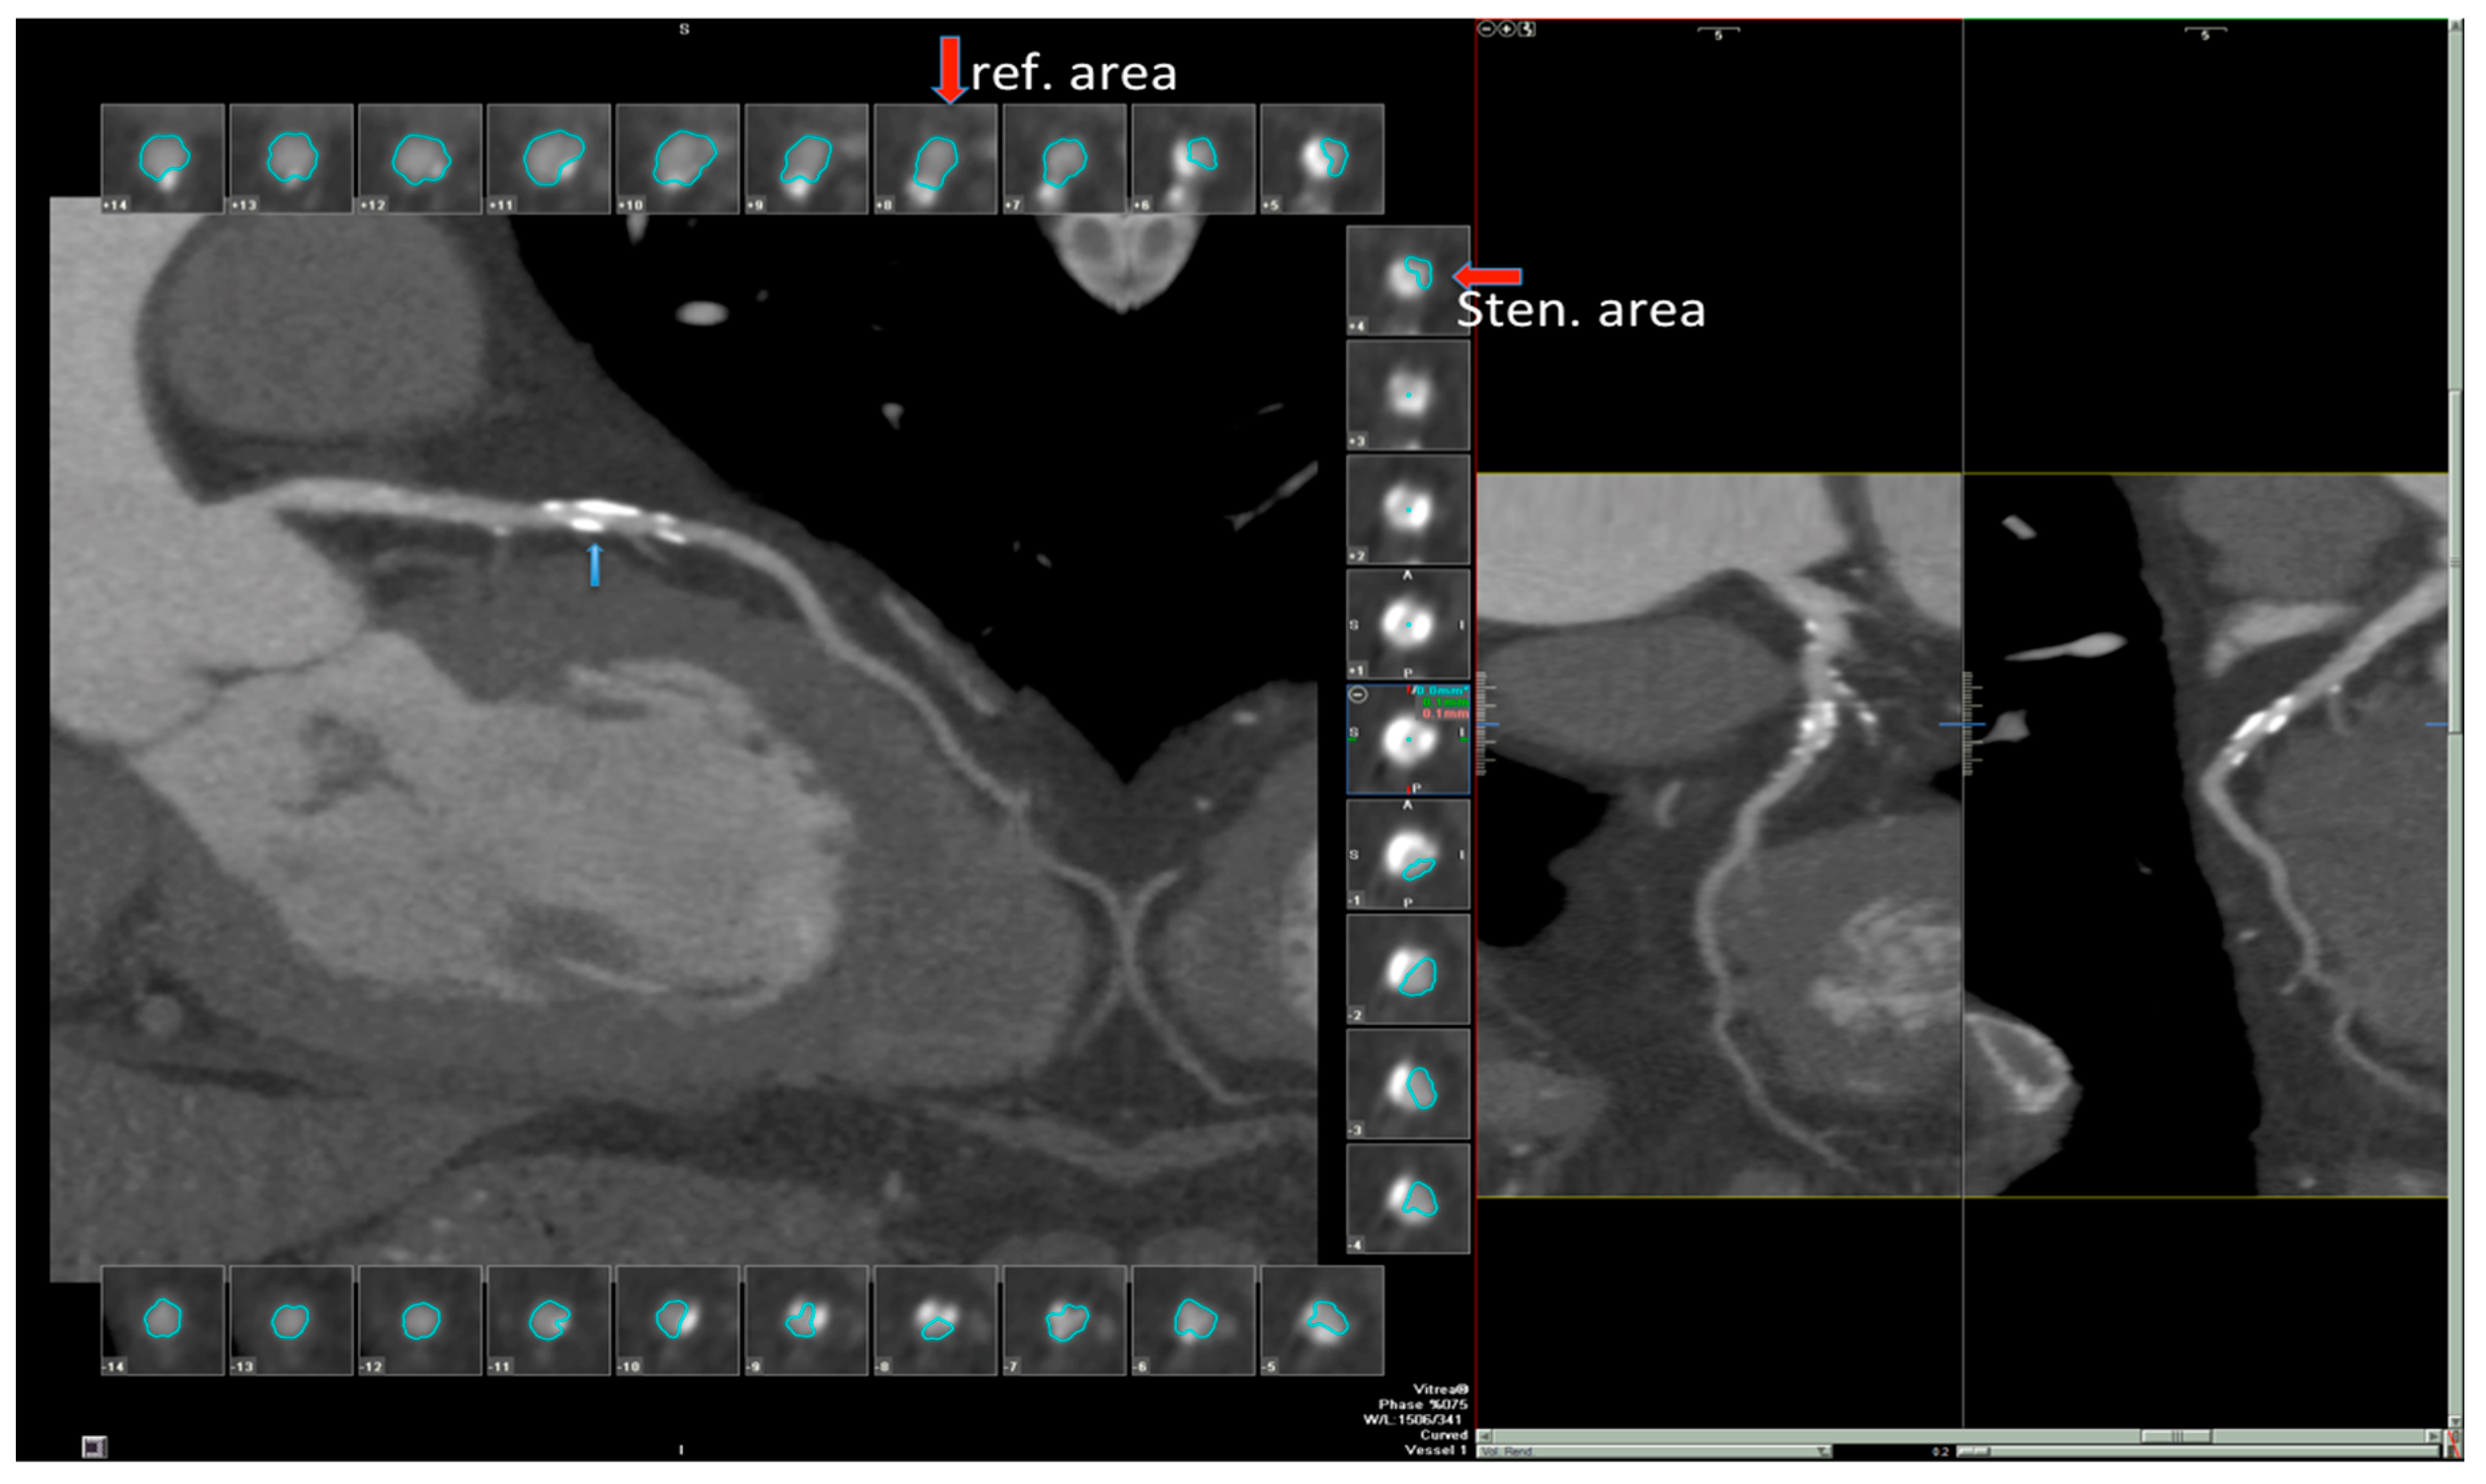

2. The Case

3.2. Computed Tomography Angiography